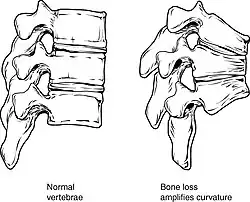

Collapse of vertebra on the right, normal on the left

Collapse of vertebra on the right, normal on the left

The main radiographic features of generalized osteoporosis are cortical thinning and increased radiolucency. Frequent complications of osteoporosis are vertebral fractures, for which spinal radiography can help considerably in diagnosis and follow-up. Vertebral height measurements can be objectively made using plain-film X-rays by using several methods, such as height loss together with area reduction, particularly when looking at vertical deformity in T4-L4, or by determining a spinal fracture index that takes into account the number of vertebrae involved. Involvement of multiple vertebral bodies leads to kyphosis of the thoracic spine, leading to what is known as dowager's hump.[117][118]

Vertebral fractures, while having a smaller impact on mortality, can lead to severe chronic pain of neurogenic origin, which can be hard to control, as well as deformity. Though rare, multiple vertebral fractures can lead to such severe hunchback (kyphosis), the resulting pressure on internal organs can impair one's ability to breathe.